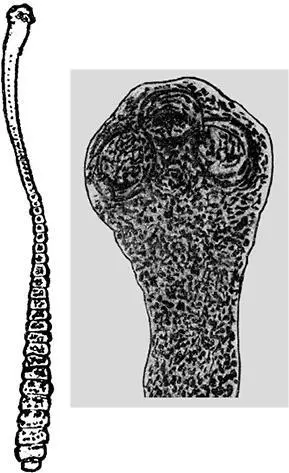

Цепень крысиный – гименолепис диминута – более грозный и более крупный по сравнению с карликовым цепнем – достигает 60 см. Впервые эти глисты были обнаружены в 1851 году Бильхарцем в подвздошной кишке мальчика, умершего от менингита.

Рис. 4. Крысиный цепень (увеличение)